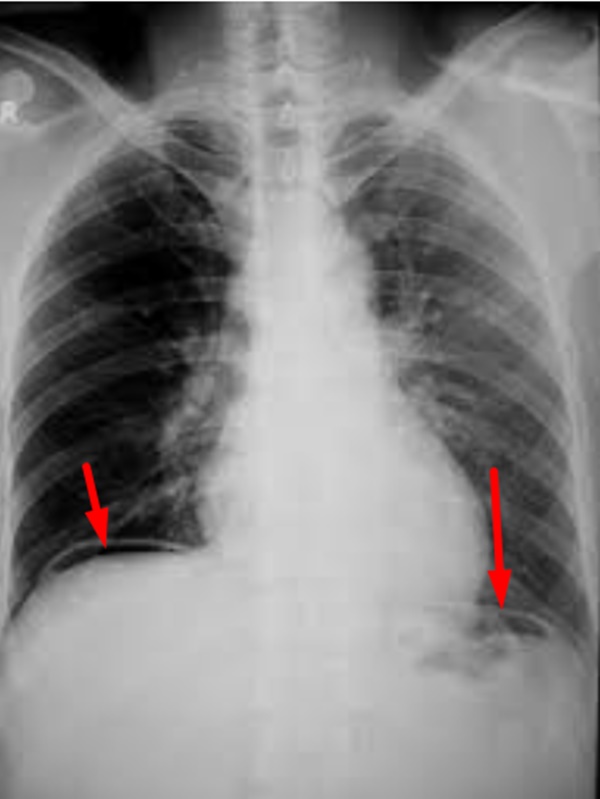

Phim chụp bệnh nhân 15 tuổi bị thủng dạ dày, ảnh BSCC.